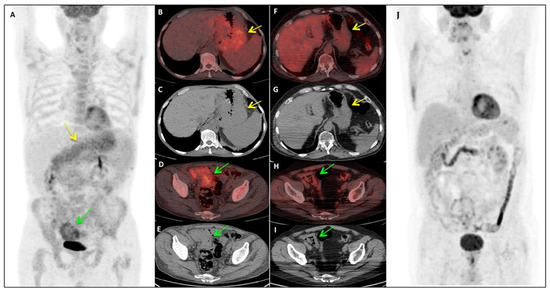

In Figure 1 is described a representative case from our cohort.

Figure 1. Pre- and post-therapy 18F-FDG PET/CT assessment in a patient affected by MCL. The patientis a 63-years old man diagnosed with a classic stage IV MCL. He presented an important gastric and intestinal involvement at staging (AE). After treatment with R-CHOP/R-DHAP, we could observe a normalization of the 18F-FDG PET/CT findings (F–J). In this patient, also gastric and colorectal biopsy were found positive. (AE) Baseline Maximum Intensity Projection (MIP)(A), axial fused PET/CT (B,D) and CT images (C,E): PET/CT demonstrated pathological 18FDG uptake (SUV max 4.9) in the whole stomach wall (B, yellow arrow), which appear thickened at the reference co-registered CT images (C, yellow arrow), as well as in the intestinal walls (SUV max 5.2) in the right iliac fossa (D, green arrow), which appear conglomerate (E, green arrow). (FJ) Post-therapy evaluation MIP (J), axial fused PET/CT (F,H) and CT images (G,I): PET/CT demonstrated complete disappearance of 18F-FDG uptake both in stomach and intestinal walls (F,H), which returned to be of normal thickening also at the co-registered CT images (G,I).